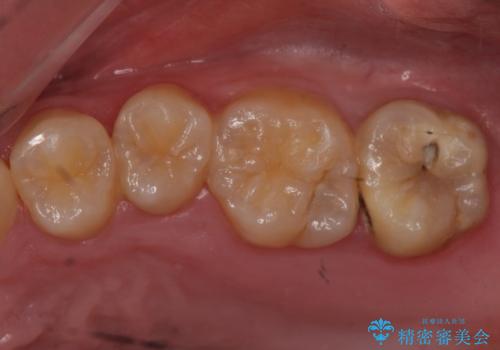

- 右下6 仮歯+セラミッククラウン 11000円+110000円費用は治療当時の料金となります

銀色だった歯が白くなったことで大変喜んでいただけました。